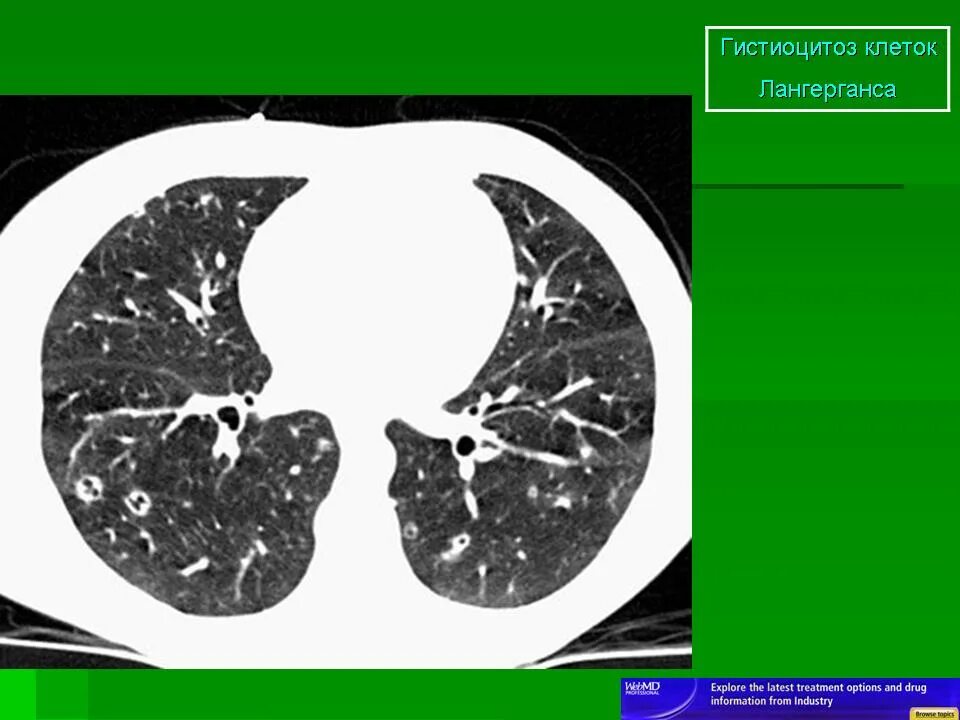

Гистиоцитоз легких